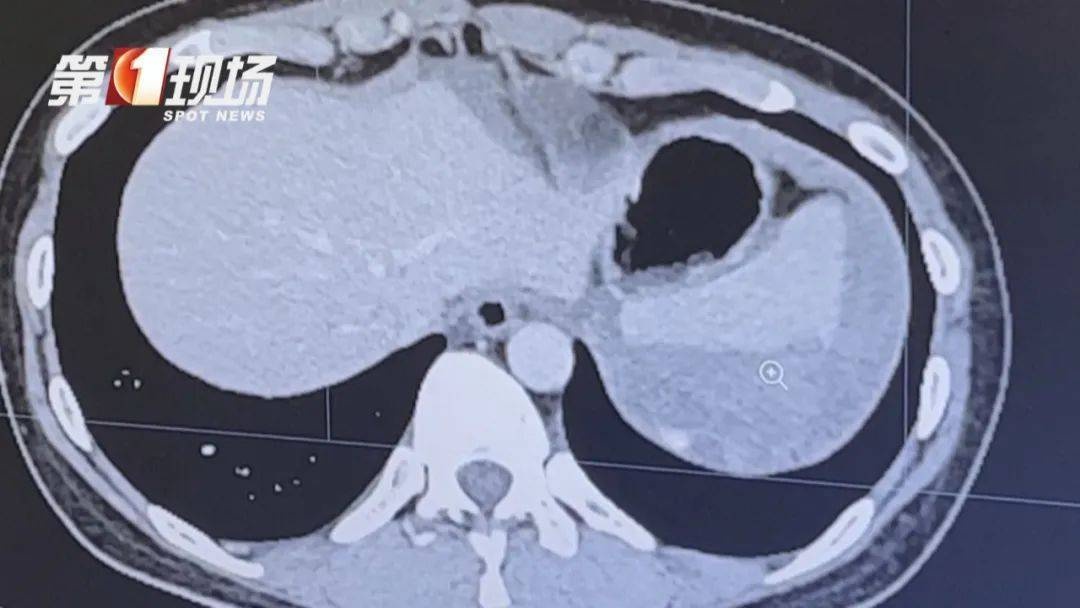

丽丽的检查结果显示情况严重,脾肝周围积聚了大量血液,且脾脏存在裂痕。面对这一危急状况,医护人员必须竭尽全力,每一项决策都直接关系到丽丽的生命安危,他们承受着极大的压力。